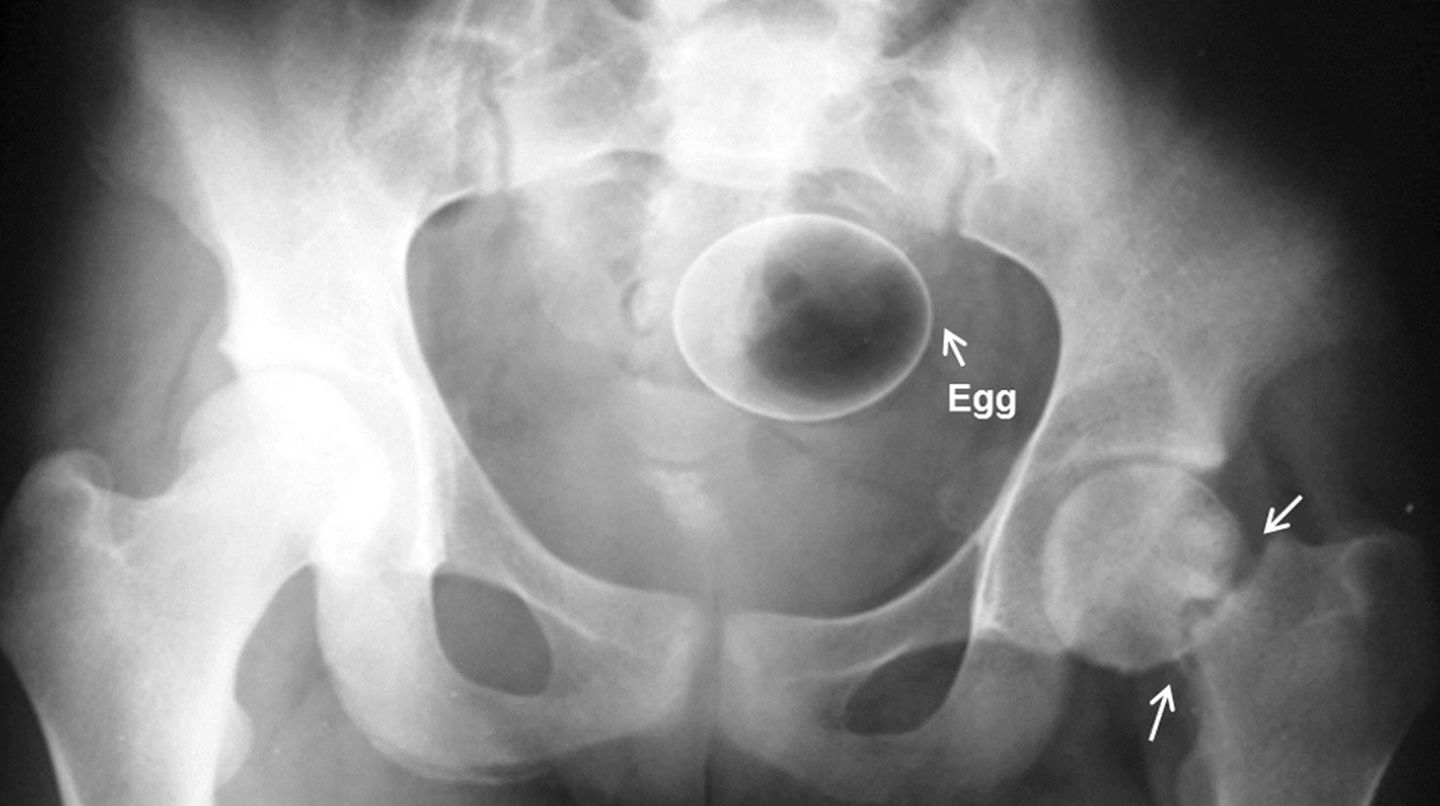

Diese Dinge gehören dort eigentlich nicht hin: Immer wieder passieren Unfälle, wenn Menschen sich zur sexuellen Stimulation über den After Gegenstände in den Darm einführen. Ob Orangen, Spraydosen oder Kaffeebüchsen - der Fantasie sind dabei offenbar keine Grenzen gesetzt.

Die Webseite radiopaedia.org zeigt, welche Dinge Ärzte auf Röntgenbildern schon entdeckt haben. Die Aufnahmen wirken skurril und erschreckend zugleich und machen deutlich, wie weit die eingeführten Dinge bereits in den mescnhlichen Darm vordringen können.

Aber Glück im Unglück für die Patienten: Die Gegenstände können meist ohne Operation entfernt werden. Sehen Sie hier einige der spektakulärsten Röntgenaufnahmen. Da runzeln selbst Chirurgen die Stirn.